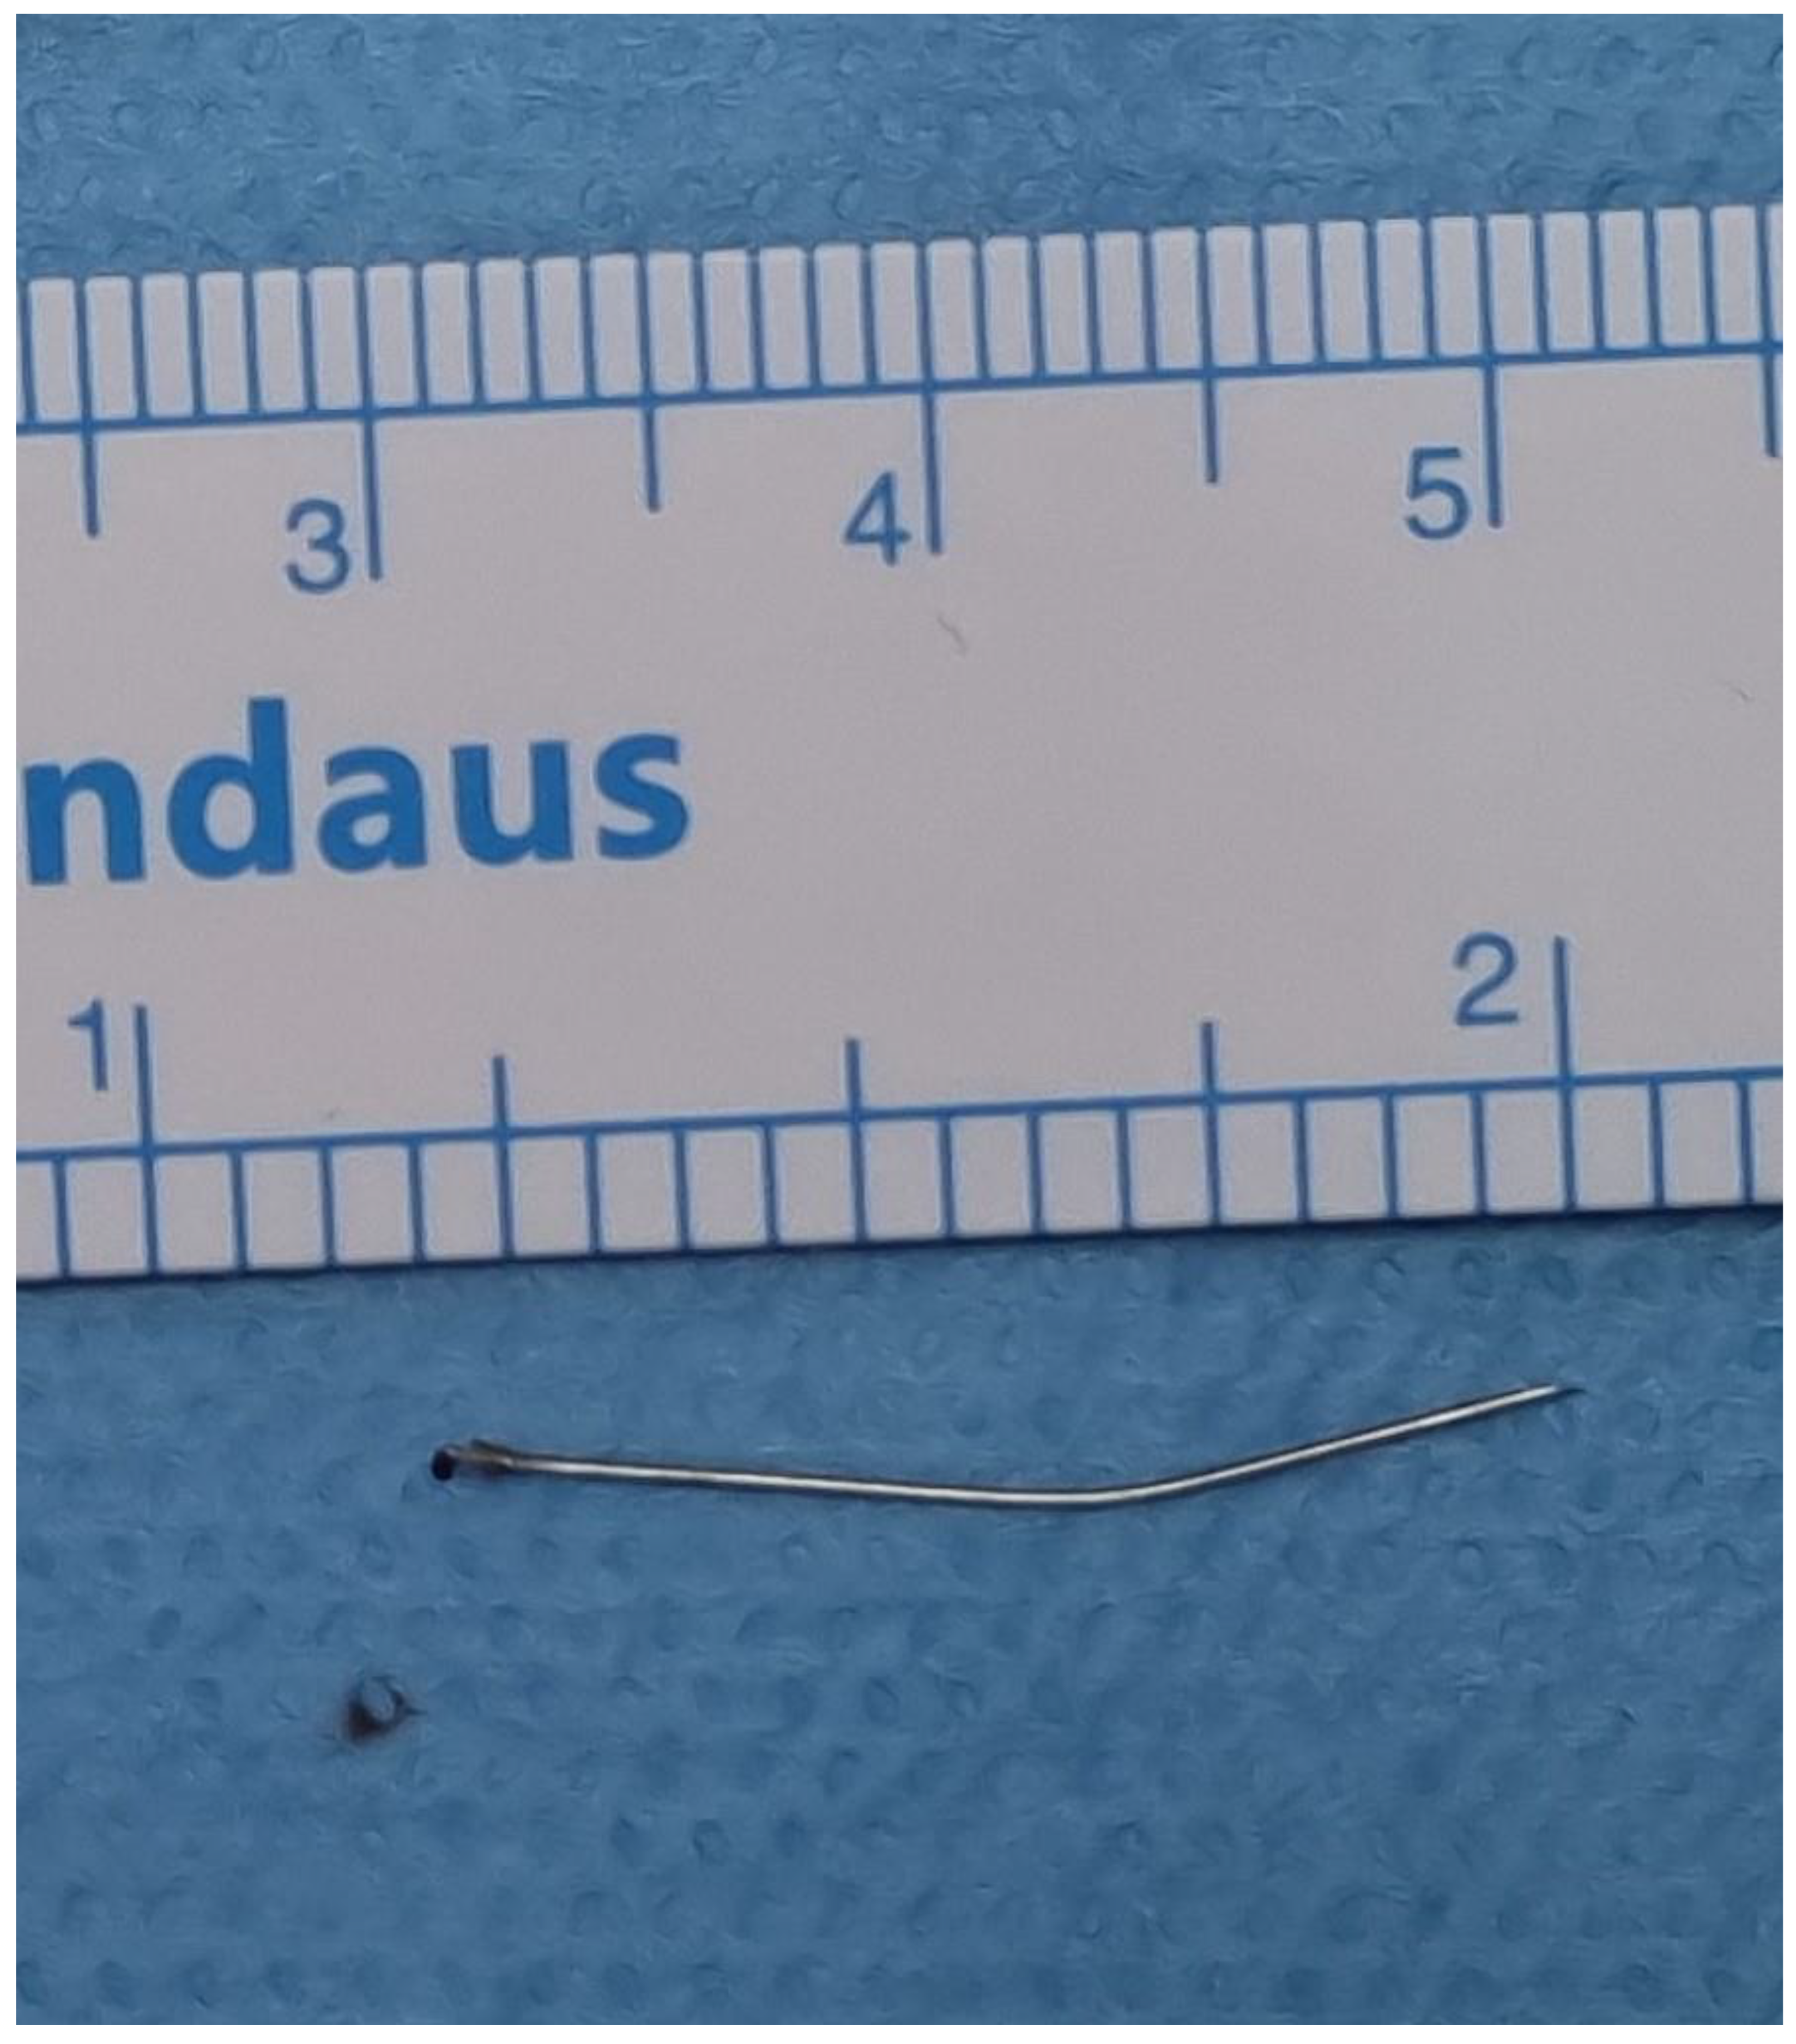

A Case of Broken Local Anesthetic Needle in the Pterygomandibular Space; Diagnostic Approaches and Surgical Management